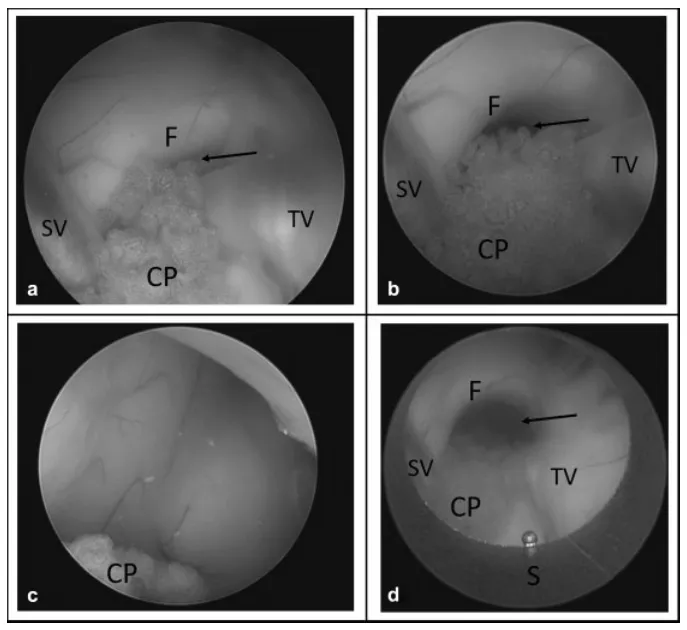

使用光学套管针及鞘管扩张小型室间孔。 (a) 室间孔过小,无法通过鞘管。在内镜直视下,将鞘管定位于室间孔中央,随后小心向前推进至第三脑室内。将鞘管退回到侧脑室后,可见扩张后的室间孔及结构完整的穹窿。箭头指示室间孔。缩写:CP,脉络丛;F,穹窿;S,内镜鞘;SV,隔静脉;TV,丘纹静脉。